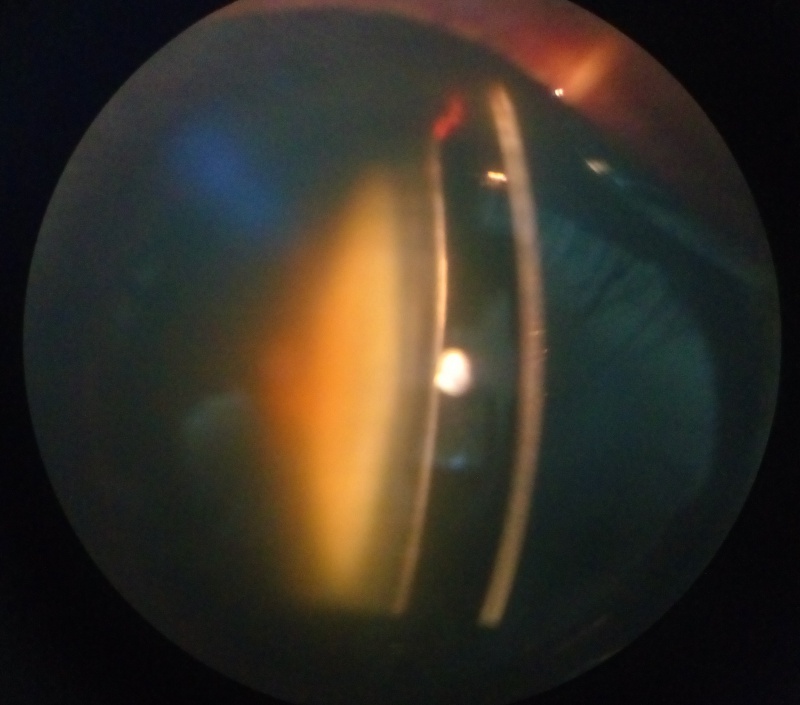

أحد مسببات الجلوكوما (الماء الأزرق) وجود تضيق في مجرى زاوية العين، خصوصاً عند المرضى المصابين بطول النظر قد يرتفع ضغط العين بشكل مفاجئ وبدرجات عالية بسبب انسداد زاوية العين، مما يؤثر على العصب البصري أحد طرق علاج المشكلة أن يتم اجراء ثقب صغير في طرف قزحية العين بالليزر

الماء الابيض (الساد) نقصد به عتامة بالعدسة داخل العين هذه العتامة تأتي بصور وأشكال مختلفة، بعضها يؤثر على حدة الابصار أكثر من غيرها بشكل عام كلما كانت العتامة قريبة للنقطة العقدية Nodal point (عند مؤخرة العدسة) كلما زاد تأثيرها على حدة الابصار حتى لو كانت العتامة بسيطة

بعد عمليات سحب الماء الأبيض يتم زراعة عدسة داخل العين لتصحيح النظر أنواع وتقنيات العدسات المزروعة متعددة البعض يعطي رؤية أوضح للبعيد فقط، وتقنيات أخرى تعطي رؤية بجودة أقل لكن تمكن المريض من رؤية الأشياء القريبة لا يوجد نوع مثالي فكل نوع له سلبياته وإيجابياته قد يكون هناك